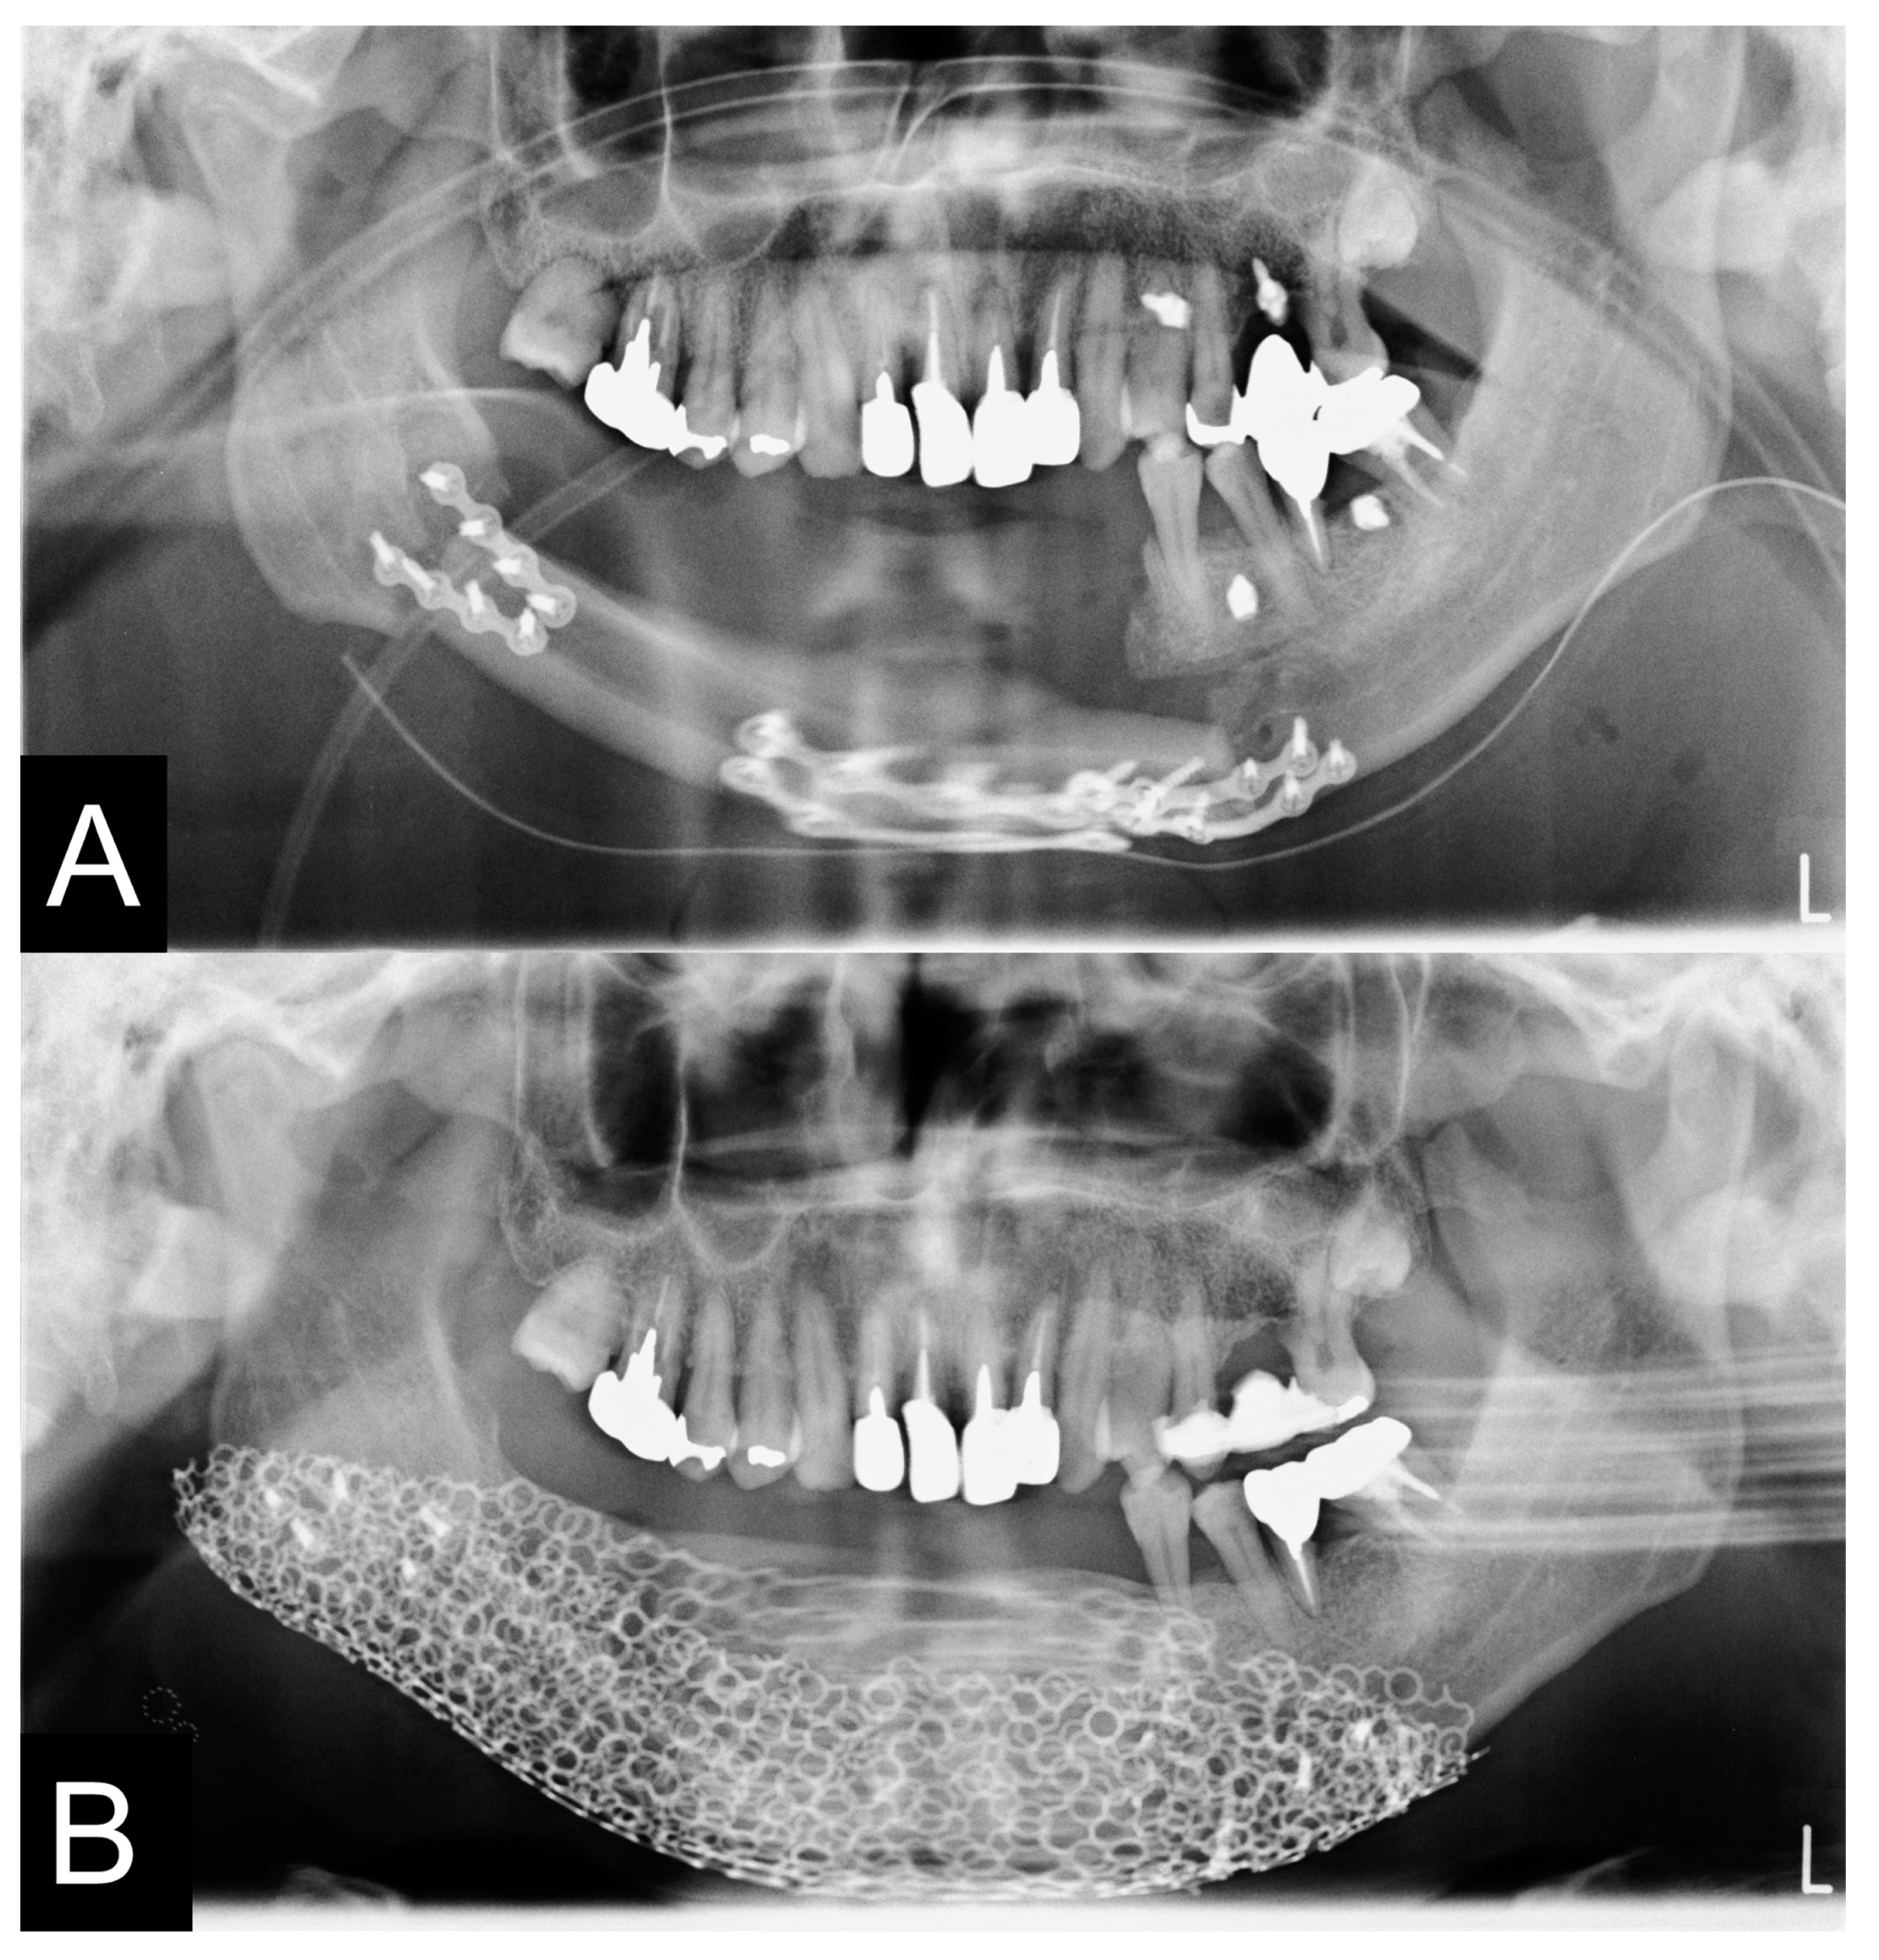

2.9. Evaluation of Mandible

3.3. Evaluation of Reconstructed Mandible